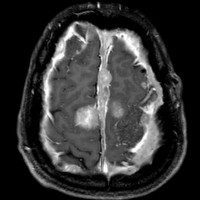

NF-2で脳腫瘍と間違っていはいけない大脳の病変

- NF-1よりずっと少ないのですが,NF-2でも大脳の病変はしばしばみられます

- MRIでグリオーマのようにみえますがそうではありません。T2強調画像で白く見えてガドリニウム造影されないのが一般的な特徴です

- 微小過誤腫 (microhamartoma)とか皮質異形成 (cortical dysplasia)とか血管周囲腔拡大 (Virchow-Robin space enlargement)とかいわれるものです

左側の病変はおそらく皮質異形成 cortical dysplasiaで,右中央寄りの病変はVirchow-Robin spaceの拡大です。